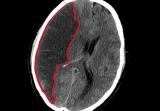

Согласно данным исследования, недавно опубликованного в British Journal of Anaesthesia, пожилые люди, перенесшие операцию с применением общей анестезии, могут испытывать умеренное истончение коры головного мозга...